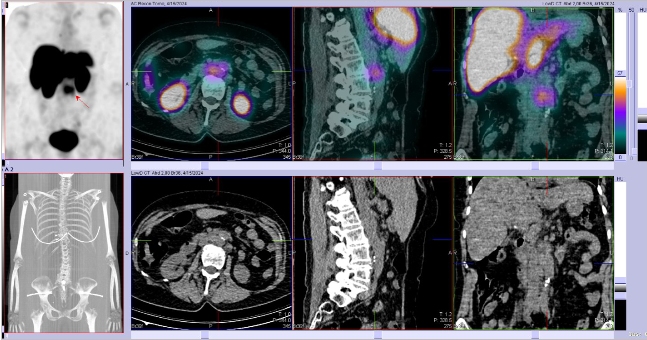

/ Obr. č. 4: Fúze SPECT/CT 4 hod. po aplikaci OctreoScanu. /

Popis: pozorujeme patologická ložiska zvýšené depozice radiofarmaka-nově nekontrastně ve více LU v levém nadklíčku, v jedné parasternální LU vpravo (úroveň Th6) vel. 10 mm, v LU v dolním mediastinu prekardiálně cca 17 mm, tomograficky zachycena chabě zvýšená akumulace RF v Th páteři v úrovni obratlového těla Th7 a Th8 (v ldCT bez patologického korelátu, nově však v ldCT obraze zjištěna v. s. lýza pravého postranního výběžku obratle Th8), v levém jaterním laloku - S4b, v pravém jaterním laloku - S5 a S6, v LU paraaortálně v úrovni L2/3 15,5 mm - dnes okrsek nápadnější, chabě v levé kosti kyčelní dorsálně při SIS - částečná regrese od min. vyšetření.

Nález svědčí pro přítomnost vícečetných patologických ložisek zvýšené denzity somatostatinových receptorů ve výše uvedených lokalizacích. Ve srovnání s posledním vyšetřením jsou detekována nová ložiska v levém nadklíčku a mediastinu, susp. diskrétní nález i v Th páteři (obratel Th7 a Th8) se zachycenou lýzou postranního výběžku obratle Th8 vpravo v CT obraze, částečná regrese okrsku v levé kosti kyčelní oproti minulému vyšetření.

Závěr:

U nyní 70leté ženy s neuroendokrinním tumorem nejasného primárního zdroje prokazujeme progresi nálezu oproti vyšetření před 22 měsíci.